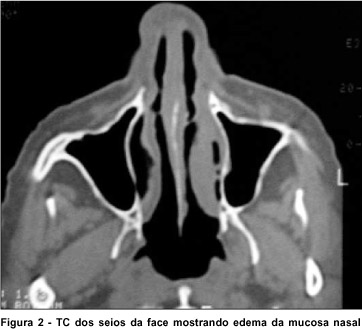

Exame nasofibroscópico, solicitado devido ao quadro de obstrução nasal crônica, mostrava acentuados eritema e edema de mucosa, também observado na tomografia computadorizada (TC) dos seios da face (Figura 2), micro-ulcerações e abundante formação de crostas fibrinoleucocitárias, meatos inferiores completamente ocluídos por edema e crostas, não sendo possível identificar o óstio lacrimal de ambos lados. Também foi realizada biópsia da cavidade nasal, com exame histopatológico evidenciando mucosa malpighiana com granulomas e processo inflamatório crônico não específico, no estroma.